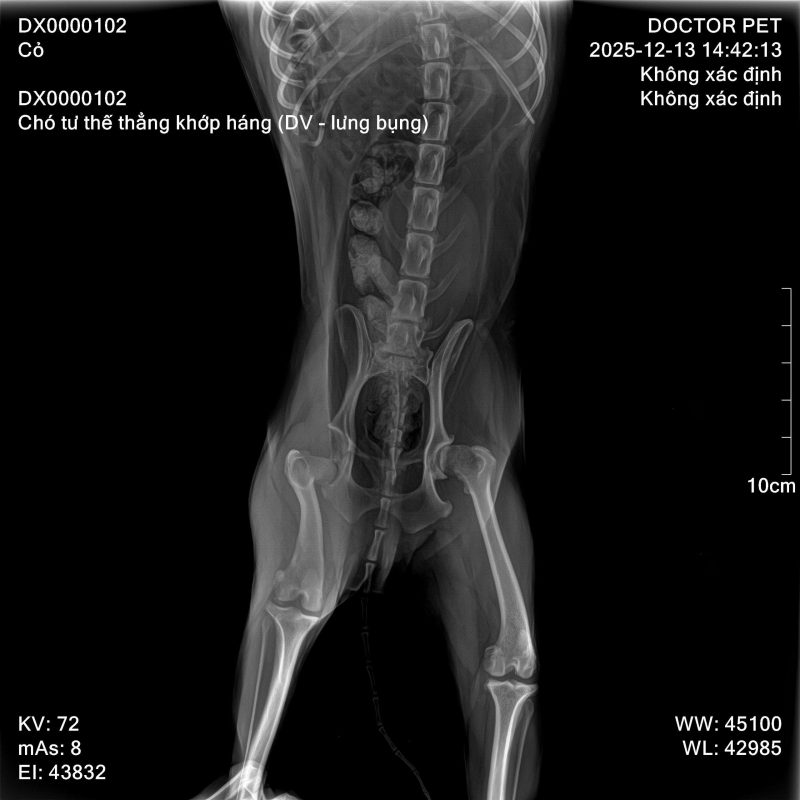

✔ Chụp X-quang xương khớp

✨ X-quang – kiểm tra xương khớp tại chỗ